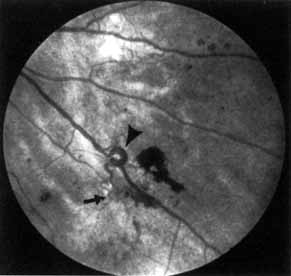

In advanced NPDR, signs of increasing retinal hypoxia appear, including multiple retinal hemorrhages, cotton-wool spots (Fig. 7), venous beading and loops (Figs. 7 and 8), intraretinal microvascular abnormalities (IRMA) (see Figs. 7 and 8), and large areas of capillary nonperfusion.

Fig. 7 A. Severe nonproliferative retinopathy with venous dilatation and beading, soft exudates, and intraretinal microvascular abnormalities B. The midphase of the angiogram shows the intraretinal microvascular abnormalities (IRMA) and severe capillary nonperfusion.

Fig. 8 Venous loop (large arrow) and intraretinal microvascular abnormalities (IRMA; small arrow).

Venous beading (see Fig. 7) and venous loops (see Fig. 8) indicates sluggish retinal circulation and are nearly always adjacent to extensive areas of capillary nonperfusion. Focal vitreous traction is thought to contribute to their formation.9 Capillaries next to areas of nonperfusion that dilate and function as collaterals are referred to as IRMA. They are frequently difficult to differentiate from surface retinal neovascularization. Fluorescein, however, does not leak from IRMA but leaks profusely from neovascularization (see Fig. 7).